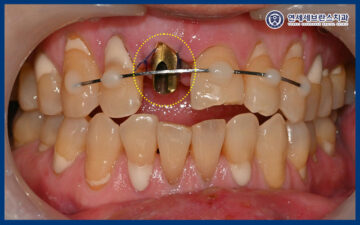

또한 치아가 정출된 부위는

재위치 후, 앞니 6개 스프린트를 부착하여

4주간 고정하여 치료를

진행하기로 하였습니다.

그리고 정출된 앞니를 재위치 시킨 후

스프린트를 이용해 고정까지 진행 후

마무리하였습니다.